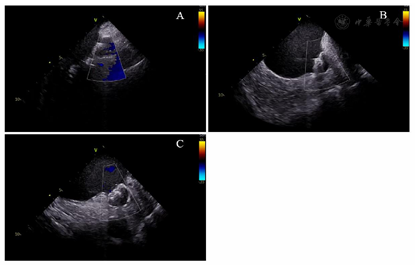

在局部麻醉下穿刺双侧股静脉,经左侧股静脉通路置入6 F静脉血管鞘,沿鞘送入10级可调弯冠状窦电极,经右股静脉通路分别置入2根8.5 F Swartz长鞘,使用Brockenbrough针行两次房间隔穿刺。静脉注射肝素,使ACT维持在300~350 s。在导丝引导下将Swartz鞘送入左房,撤出导丝和Brockenbrough针,经Swartz鞘分别放入Lasso环状标测电极(美国强生公司)和Smarttouch压力消融导管(美国强生公司)。在Carto 3D三维标测系统(美国强生公司)指导下,使用Lasso电极构建左房和肺静脉的三维解剖模型,放置Lasso电极于左右肺静脉口部,消融电极沿左右肺静脉行环肺静脉电隔离,终点为肺静脉内与左心房传导双向阻滞。消融后患者心律仍为房颤心率,给予双向150 J同步直流电复律后转为窦性心律。观察20分钟,反复心房程序刺激未诱发房性心动过速,再次验证四支肺静脉电位未恢复,房颤消融手术成功。撤出Lasso电极,换11 F鞘管,将ICE电极经鞘管送入左房,分别以45°、90°和135°测量左心耳口部直径分别为20.77、20.62、20.19 mm,深度为24.23、25.28、24.37 mm(图1)。与术前经食道超声所测的左心耳大小数据相似度较高。留置导丝至左上肺静脉,退出鞘管,经导丝送入14 F Watchman输送鞘至左心房,经鞘管和导丝送入5 F猪尾导管至左房,退出导丝调整猪尾导管至左心耳,右前斜30°、足位20°造影显示左心耳形态为单分叶风向袋型,测量口部直径为21.62 mm,深度为24.83 mm,推送鞘管至左心耳内,退出猪尾导管,经鞘管推送27 mm的Watchman(美国波士顿科学)封堵器至左心耳,经X线核实位置后,缓慢释放封堵器,X线造影和ICE核实封堵器位置良好,45°、90°和135°测量均无残余分流、无露肩(图2),压缩比分别为20%、22%、20%。封堵器牵拉试验未见移位及脱落,逆时针旋转输送器并释放封堵器。观察10 min,ICE复查封堵器位置,再次测量残余分流、露肩和压缩比,与释放前相比各角度均无明显变化(图3)。术中ICE测量无嵴水肿、无心耳旁积液、无心包积液,左心耳封堵手术成功。房颤导管消融及左心耳封堵手术时间为103 min,透视剂量为356 mGy。